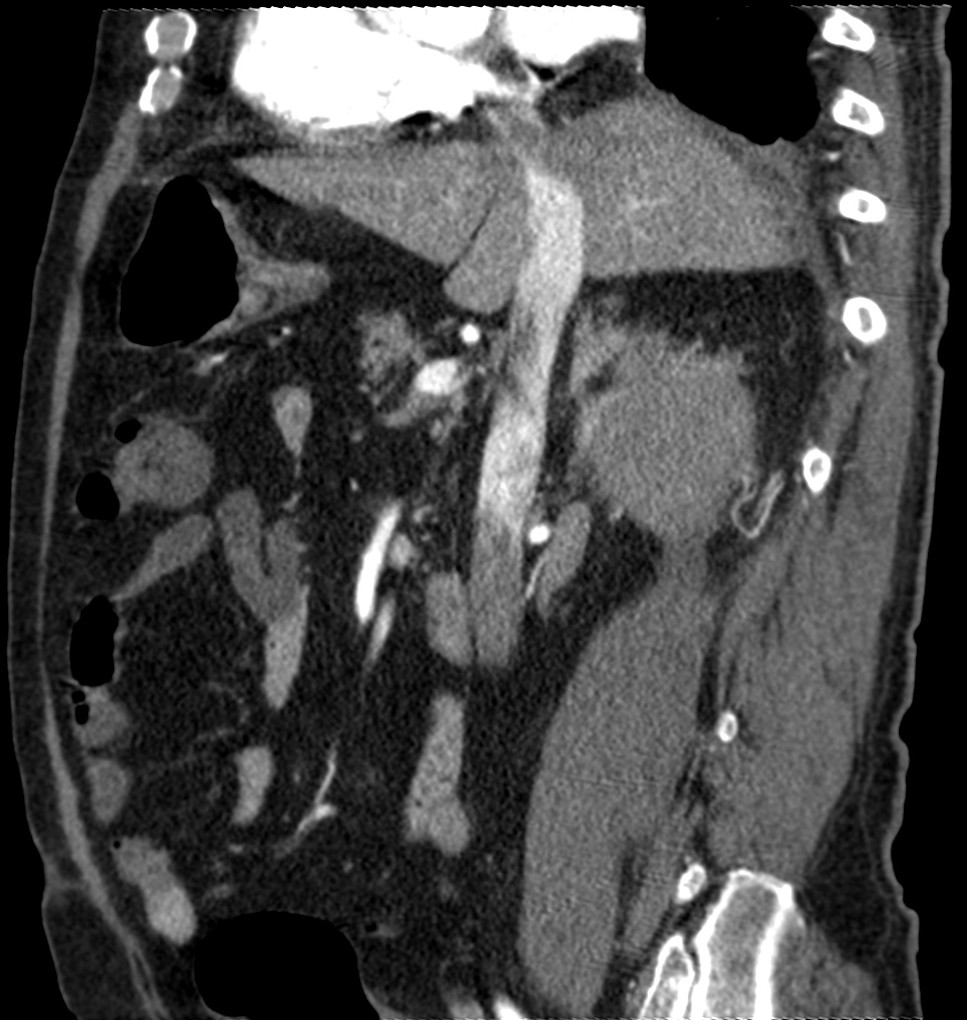

CASO 2: Paciente de 68 años con dolor en flanco izquierdo, fiebre y malestar general. A la exploración existe enrojecimiento de la piel con sensación de masa palpable y puño percusión muy positiva.

El paciente es alégrico al Iodo. Se realiza TC sin contraste para ampliar estudio.

Todos estos hallazgos están en relación con una Pielonefritis Xantunogranulomatosa que afecta al riñón derecho junto con una colección que ha fistulizado a región lumbar.

- Pielonefritis Xantunogranulomatosa.

- Es una forma infrecuente de pielonefritis crónica, de origen obstructivo, caracterizada por la formación de un absceso granulomatoso que puede extenderse al EPR-, severa destrucción renal y un cuadro clínico de fiebre, malestar general, dolor en el flanco y masa renal, a veces palpable.

- En placa simple podía verse un masa que renal con o sin borramiento de la línea del psoas. En ecografía, cálculos y aumento del tamaño renal en la forma difusa con múltiples áreas anecoicas correspondientes a las colecciones purulentas.

- Los hallazgos en TC pueden ser:

- Uni o bilateralidad de la lesión.

- Afección difusa o localizado.

- Litiasis de tipo coraliforme, calcificaciones intraparenquimatosas.

- Aumento difuso del tamaño renal.

- Áreas hipodensas o hipoecogénicas dentro de la lesión renal debidas a cálices dilatados, abscesos o áreas de necrosis parenquimatosa.

- Pobre o nula eliminación del medio de contraste en el riñón afectado.

- Compromiso inflamatorio que excede los límites del riñón y genera colecciones periféricas o extensión hacia vísceras vecinas.